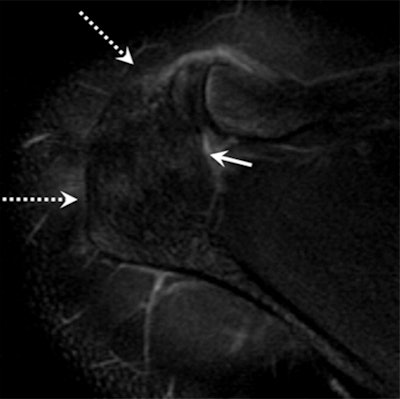

Image above shows incomplete fusion with moderate bone marrow edema in an 18-year-old male pitcher with acromial apophysiolysis. MR image below in the same patient at age 25 after quitting pitching shows complete fusion and resolution of the previously seen acromial edema (dashed arrows). Images courtesy of Radiology.

Researchers at Thomas Jefferson University Hospitals found fusion issues and soreness at the acromion, located at the top of the shoulder. Under normal conditions, the acromion develops when four individual bones fuse into one during a person's teenage years. However, MRI showed signs of acromial apophysiolysis, which is characterized by incomplete fusion and swelling.

"The two findings with MRI that make the diagnosis for us are bone marrow edema, and the fusion with the two bones of the acromion still has to be open," he said. "You can see the nonfusion [of the acromion bones] on other modalities, such as CT and x-ray, but the edema is something you cannot pick up on any other imaging modality than MRI. So MRI is necessary to make the diagnosis and cannot be replaced by any other modality, because the edema is half of the diagnosis. You definitely need to see the edema."